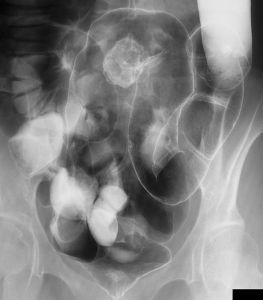

7、 前列腺結石 :出現腰骶部、會陰部疼痛及性功能紊亂如陽痿、早泄等症狀。直腸指檢可捫及前列腺有結石摩擦感,骨盆X線平片有陽性結石陰影,可資鑑別。